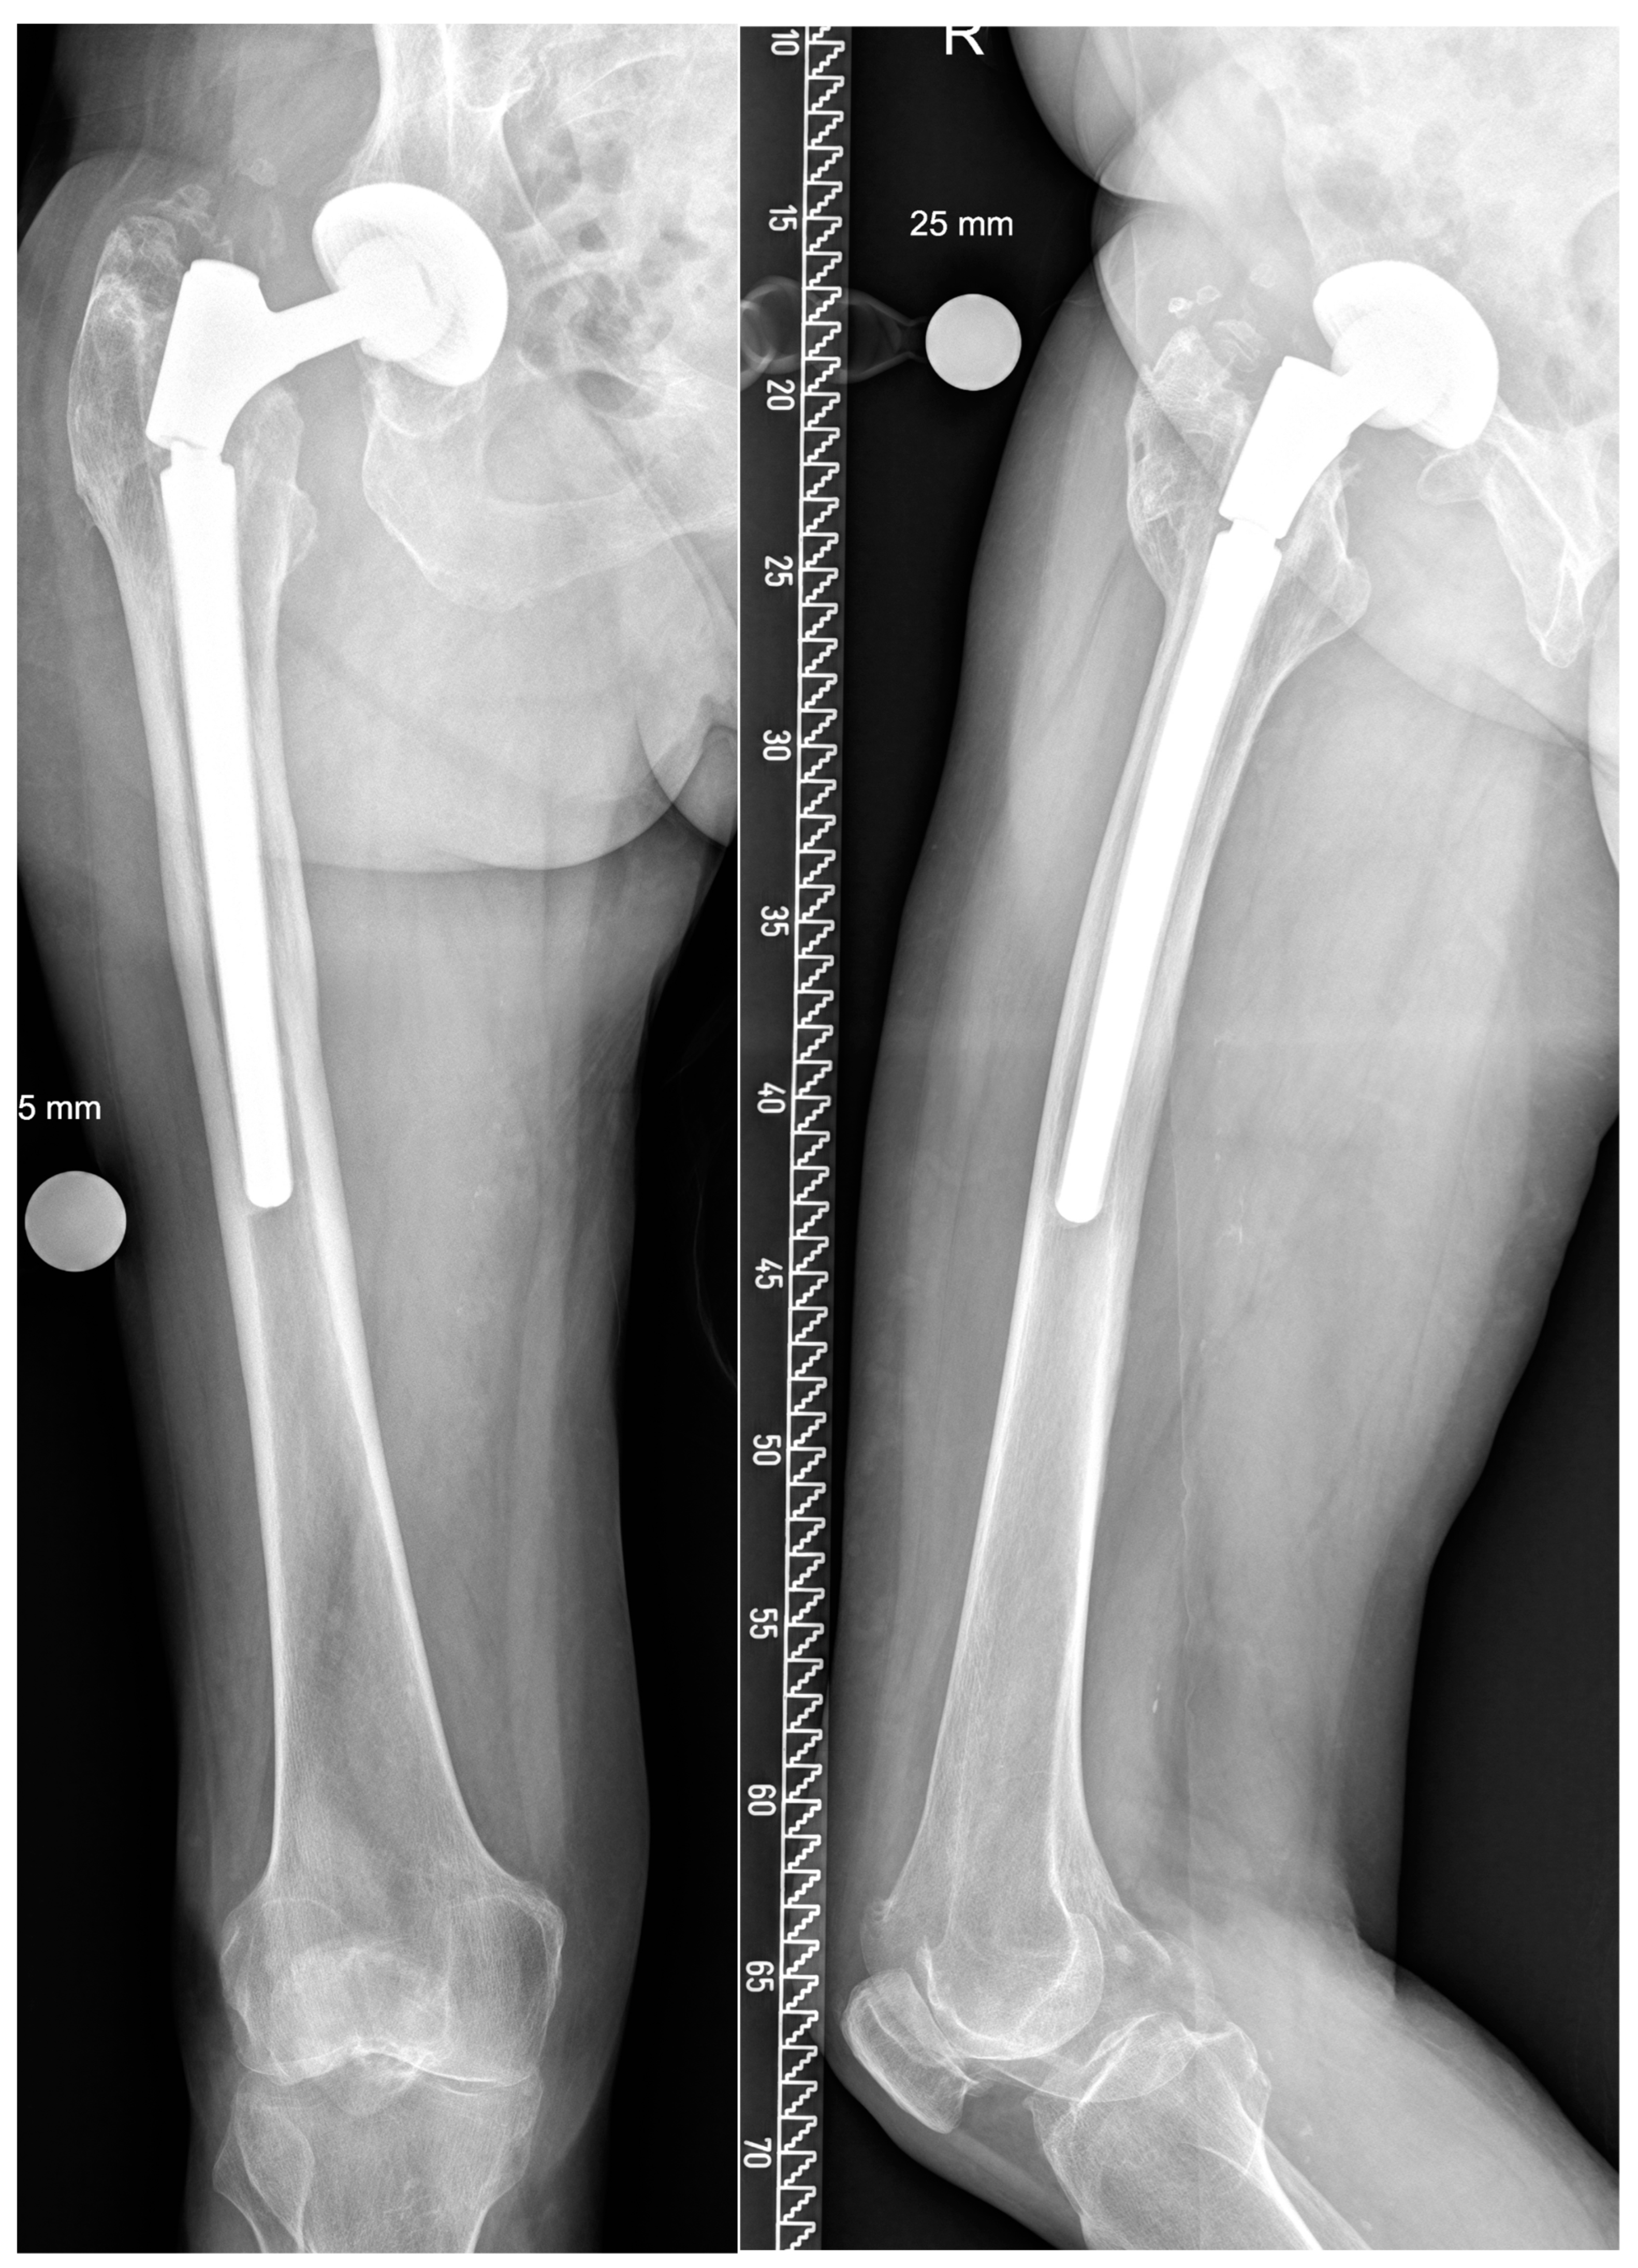

| Patients Sex, Age (Year) | Indication # | Stem Configuration * | BMI | Bone Defect | Breakage Po. (Year) |

|---|---|---|---|---|---|

| m., 82 | ppf | c, 21, 200, lat, long, m | 27 | 3A | 2.8 |

| f., 55 | al | s, 16, 140, lat, short, s | 33 | 2 | 5.4 |

| m., 58 § | al | s, 30, 200, lat, short, s | 44 | 3A | 3.5 |

| m., 47 | ts | c, 16, 200, lat, short, s | 45 | 2 | 5.5 |